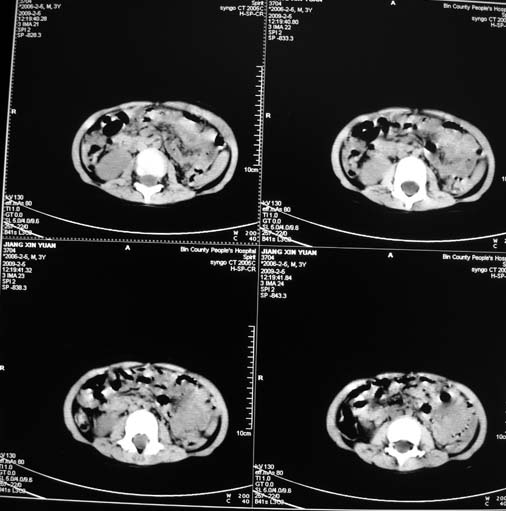

男,3岁,肾母细胞瘤术后,肝脏的低密度是什么?

胰尾下方见两枚囊形灶,肠管?病灶?左侧肾上腺区见团块状影,转移病灶?术后表现?建议与前片对比,肝脏病灶好像有牛眼表现,不除外转移,如果不增强,建议加做个b超,至少可分清其囊性或者实性,又便宜,免费自已给他弄一下也行,对诊断有帮助

左肾母细胞瘤术后:肝脏多发低密度灶,考虑转移可能性大。

左肾母细胞瘤术后:肝脏多发低密度灶,考虑转移可能.请结合临床及增强以及术前检查等